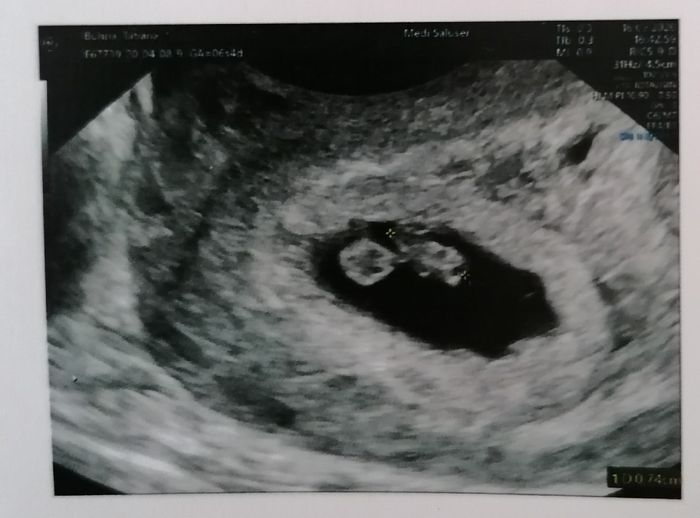

Ciao a tutte, aiutatemi a capire: inizio mese 2° biochimica oggi sono 9 pm ho qualche fastidio come se di nuovo mi dovessero venute il ciclo così ho monitorare l'ovulazione, ma mi hanno messo un po' di dubbi. Secondo voi?

Ciao ragazze, qualcuna che ha fatto monitoraggi durante l'ovulazione. 2 giorni fa ho fatto l'eco a 6 pm, ciclo post biochimica. Vedendo l'ecco mi sembra vicino alla fase ovulatoria, su indo voi?

Buongiorno a tutte e buona pasquetta, qualcuna che ha fatto monitoraggio per l'ovulazione mi sa dire se secondo lei con questa eco ero vicina all'ovulazione? Eco fatta a 5 pm.Oggi sono a 10 pm.